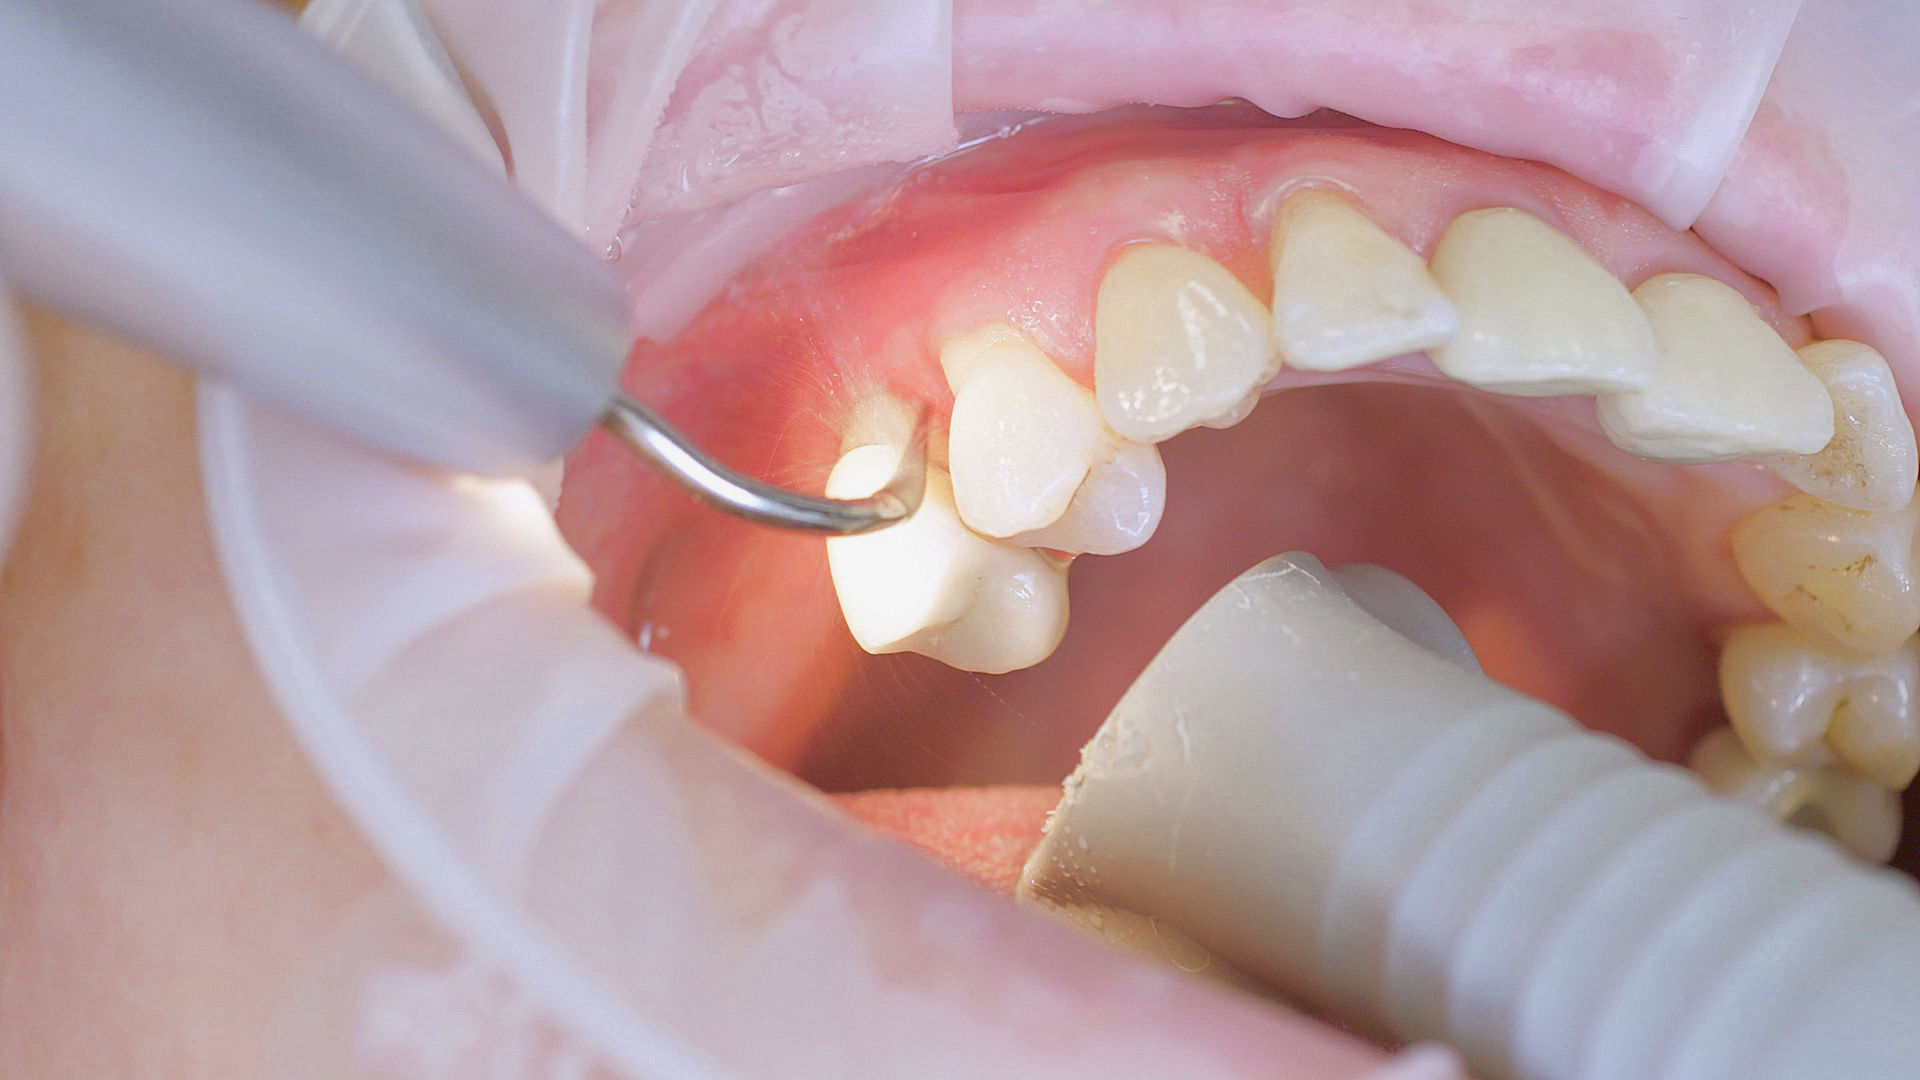

Every dental examination is based on a detailed medical history combined with targeted diagnostics con- taining as much detail as possible: The dentist records systemic risk factors such as diabetes or smoking and identifies any potential increased tendency to inflammation.[3] Hard and soft tissues are examined and periodontal pockets are probed in a screening test according to PSR (Periodontal Screening and Recording). In case of abnormal findings, the periodontal status is then re- corded and therapy is initiated where necessary. This treatment begins with professional biofilm management, by using, for example, rotary cups and polishing com pounds (Fig. 1), and comprehensive instructions in oral hygiene. Sonic or ultrasonic systems remain an effective alternative or supplement to manual instruments for sub- gingival debridement and biofilm management (presentation by Prof. Dr Ulrich Schlagenhauf;

Good individual oral hygiene and professional biofilm management

Fig. 1: Good individual oral hygiene and professional biofilm management, e.g. with cups and brushes, helps support periodontal and peri-implant health.